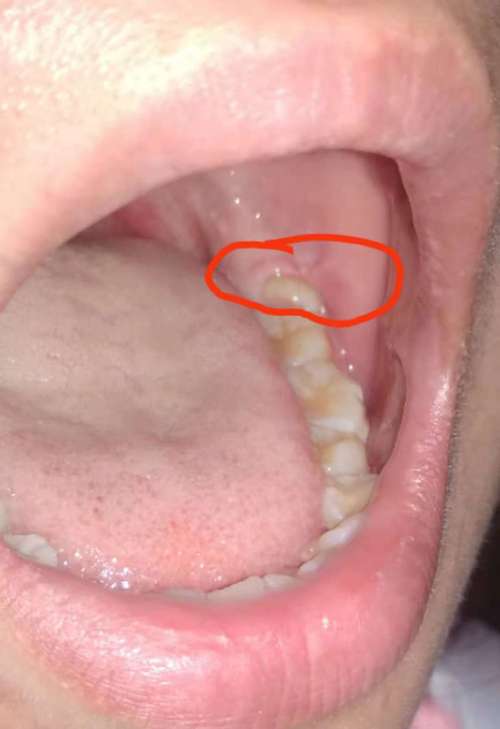

很多人在完成正畸治疗,摘下牙套后,突然发现后槽牙区域冒出了新的牙齿,或牙龈肿痛、不适,去检查后被医生告知是“智齿萌出”,这让人困惑:“明明正畸前拍片没长智齿,怎么矫正完突然长了?”智齿并非“突然”生长,而是正畸过程中的口腔变化让它从“潜伏”到“显现”,或是加速了它的萌出进程,要理解这一现象,需从智齿的生长规律、正畸治疗的影响以及应对策略说起。

智齿是人类的第三磨牙,通常在17-25岁萌出,这一阶段被称为“智齿萌出期”,但并非所有人的智齿都会顺利萌出:部分人先天缺失智齿(上颌或下颌),部分人的智齿因颌骨空间不足而“阻生”(埋在牙槽骨内或牙龈下),无法正常长出,正畸前,医生通常会拍摄全景片(X光片)检查牙齿情况,若智齿完全埋伏在颌骨内且未对邻牙造成压迫,可能暂时无需处理,这也让患者误以为“自己没长智齿”。

三是口腔环境变化刺激,正畸期间,戴矫治器时口腔清洁难度增加,牙龈易出现轻微炎症;摘除矫治器后,牙龈形态恢复,若智齿周围牙龈有红肿或异物感,更容易被注意到,正畸后牙齿排列整齐,原本被拥挤牙齿“遮挡”的智齿,在清晰视野下更易被发现。